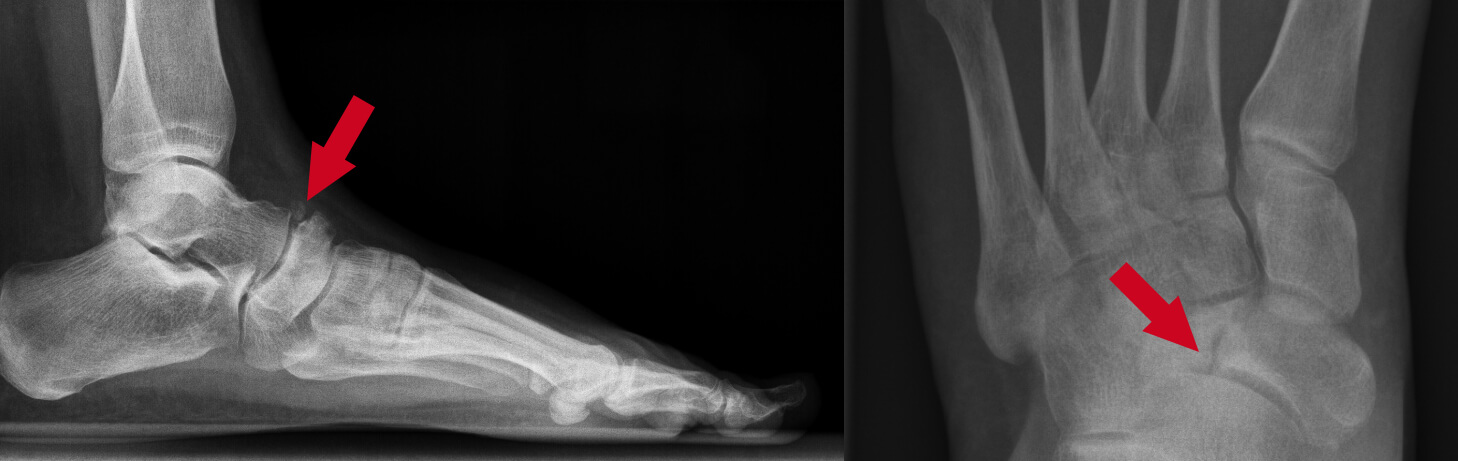

Dit is een voor-achterwaartse röntgenopname van een voet met de ziekte van Müller-Weiss in een begin stadium. Op de rechter foto bevindt zich een ’spleetje’ (fissuur of breuk) in het schelpvormig beentje. Het gedeelte van het botje aan de linker zijde van de breuk zal verder afsterven.